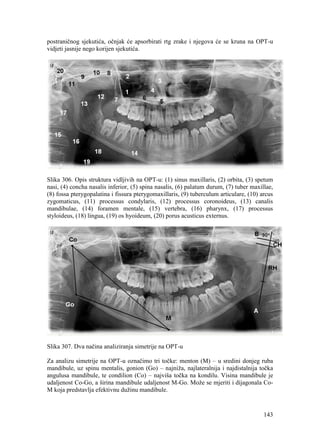

Am J Orthod Dentofacial Orthop. 2006;130:594-602.

47

4. MOBILNE FUNKCIONALNE NAPRAVE

KONSTRUKCIJSKI ZAGRIZ